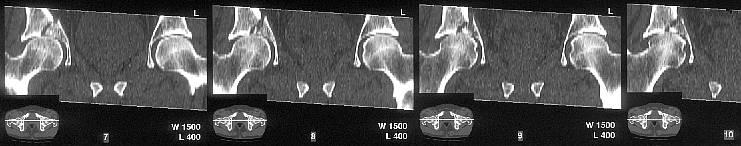

The CT scan confirms what the iliac oblique showed - the acetabulum is incongruous, and the femoral head is following the caudal piece medially. The other thing the femoral head is doing is grinding up against that displaced fracture. This is going to lead to erosion of the femoral head cartilage, and rapid onset of post-traumatic arthritis.

How long will it take? I've seen it happen in less than a year.

Yes it does. The CT scan reveals a fracture through the weight bearing dome.

My mail was based on the first mail from Alo Kullerkann before the CT pictures were avilable on the net. Later I saw the CT pictures and realised that weight bearing areas were involved.